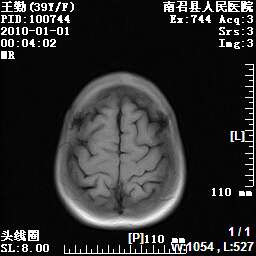

以下是引用随光逐影在2010-1-22 9:03:00的发言:[br]考虑左侧中颅窝(蝶骨翼区)脑膜瘤侵犯蝶骨翼并突入左侧眼眶。

以下是引用水过无痕在2010-1-22 14:55:00的发言:[br]一、定位:颅外占位;二、定性:恶性可能性大;三、组织来源:来源于左侧眼外直肌或其他部位;考虑为:横纹肌肉瘤>转移瘤>脑膜瘤.